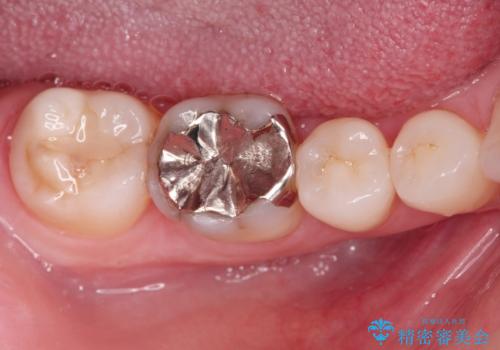

ご希望に沿って、ゴールドインレーにて治療を行いました。

- PGA(ゴールド)インレー 6.6万円 × 2本費用は治療当時の料金となります

ゴールドインレーは適合がよく、強度もあり、腐食もしにくく、アレルギーのリスクが極めて少ない安定した治療法です。虫歯の再発リスクを減らすことができます。